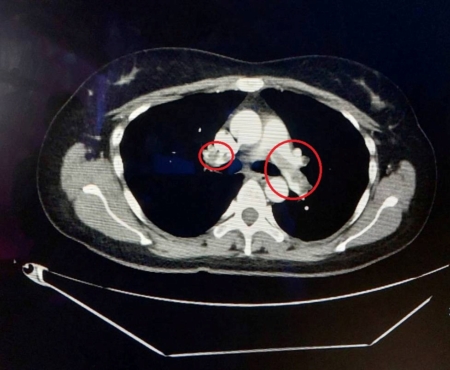

【大紀元2025年07月23日訊】(大紀元記者陳文敏綜合報導)76歲的黃伯伯因長期氣喘及走路很喘而就醫,檢查發現雙側的肺動脈竟有大量的血栓,必須立刻接受治療;另一位32歲的劉小姐則因躺在床上會喘,且呼吸變得困難而到急診就醫,同樣在肺動脈發現血栓,導致肺栓塞。大千綜合醫院心臟外科主任李俊毅提醒,肺動脈栓塞是一種威脅生命的急性疾病,造成的影響從咳嗽、呼吸喘到猝死都有可能發生!

治療方式可分為抗凝血藥物治療、血栓溶解藥物治療、外科治療。此次案例中的76歲病人,因為屬於慢性血栓,無法以藥物治療,所以採用自費微創智慧血栓清除系統,以抽吸的方式直接移除陳舊已久的血塊。病人治療前血氧已降到80%,遠低於正常人的95%~100%,當雙側血栓移除完成時,病人血氧立即恢復正常,走路距離長也不覺得喘。另一位32歲的病人,是因小腿骨折手術後行動不便,就長時間躺臥在沙發上,先是手術的腳發生腫痛,然後就開始出現呼吸喘的症狀。由於血栓形成的時間小於2週,加上骨科手術部位穩定,因此先放置下腔靜脈濾網,避免下肢靜脈血栓再跑到肺部,再使用自費超音波震盪溶栓導管搭配血栓溶解藥物治療。病人2天後移除導管,透過肺動脈造影檢查,確認血栓已完全溶解,肺部血流流動正常,並於隔天出院返家。